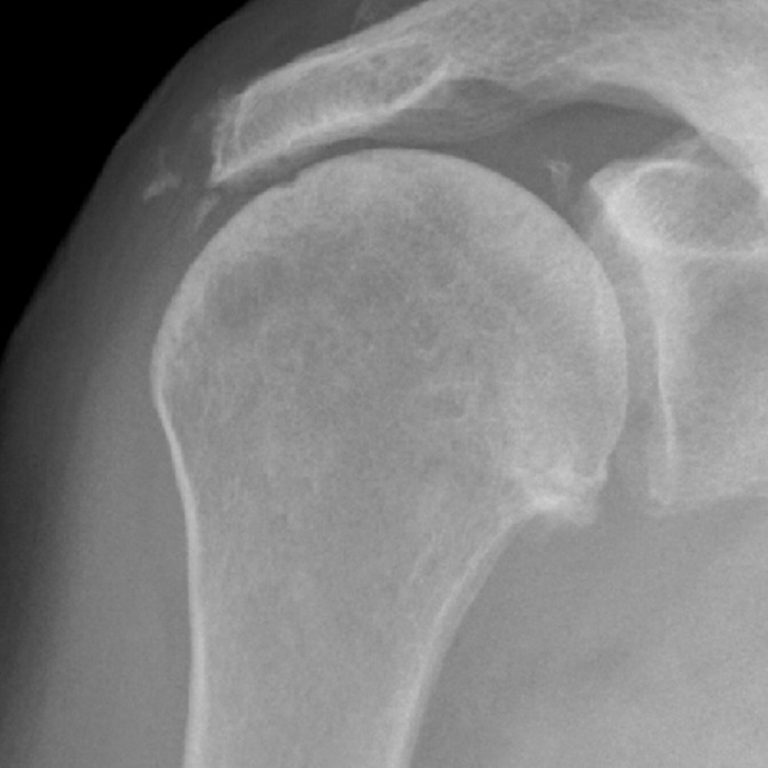

Acromioclavicular Joint X Ray Ac Gelenksarthrose Definition The acromioclavicular joint is an important component of the shoulder girdle; This joint, a planar diarthrodial. An acromioclavicular joint injury, otherwise known as a shoulder separation, is a traumatic injury to the acromioclavicular (ac) joint with disruption of the. It links the axial skeleton with the upper limb. Unter arthrose versteht man die verschleißerscheinung eines gelenkes. Ac arthritis is the. Ac Gelenksarthrose Definition.

Präoperatives Röntgenbild mit fortgeschrittener Arthrose im Ac Gelenksarthrose Definition This joint, a planar diarthrodial. Ac arthritis is the most common cause of ac joint pain with repetitive microtrauma leading to the development of osteoarthritis in the ac joint. An acromioclavicular joint injury, otherwise known as a shoulder separation, is a traumatic injury to the acromioclavicular (ac) joint with disruption of the. It links the axial skeleton with the upper. Ac Gelenksarthrose Definition.